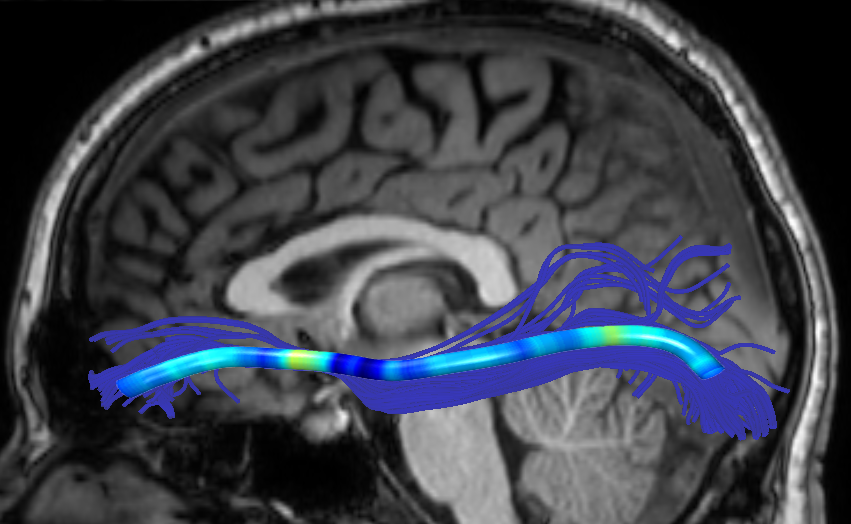

We performed pairwise comparison between two scans of a 32-year-old basketball player, diagnosed with mild occipital traumatic brain injury and frontal hemorrhage due to contrecoup impact, acquired one week and 6 months post-injury. The hemorrhagic lesion at the frontal right hemisphere of the player is no longer visible in the FLAIR image acquired 6 months after injury (Fig. 2a). Local differences between corresponding, longitudinal FA- and MD-FFDD profiles of the FMT (chosen due to its proximity to the lesion area) are shown in Fig. 2d. Figs. 2b-c present color-coded FMT to visually demonstrate these differences. Results show significant longitudinal variability at the right hemisphere part of the tract, corresponding to the lesion area, and relatively minor differences along the rest of the tract. These results should be considered as a proof of concept, validating the FFDD analysis results for the detection and localization of mTBI-related variabilities between fiber bundles.

| (a) FLAIR | (b) FA-FFDD | (c) MD-FFDD | (d) Local Differences |